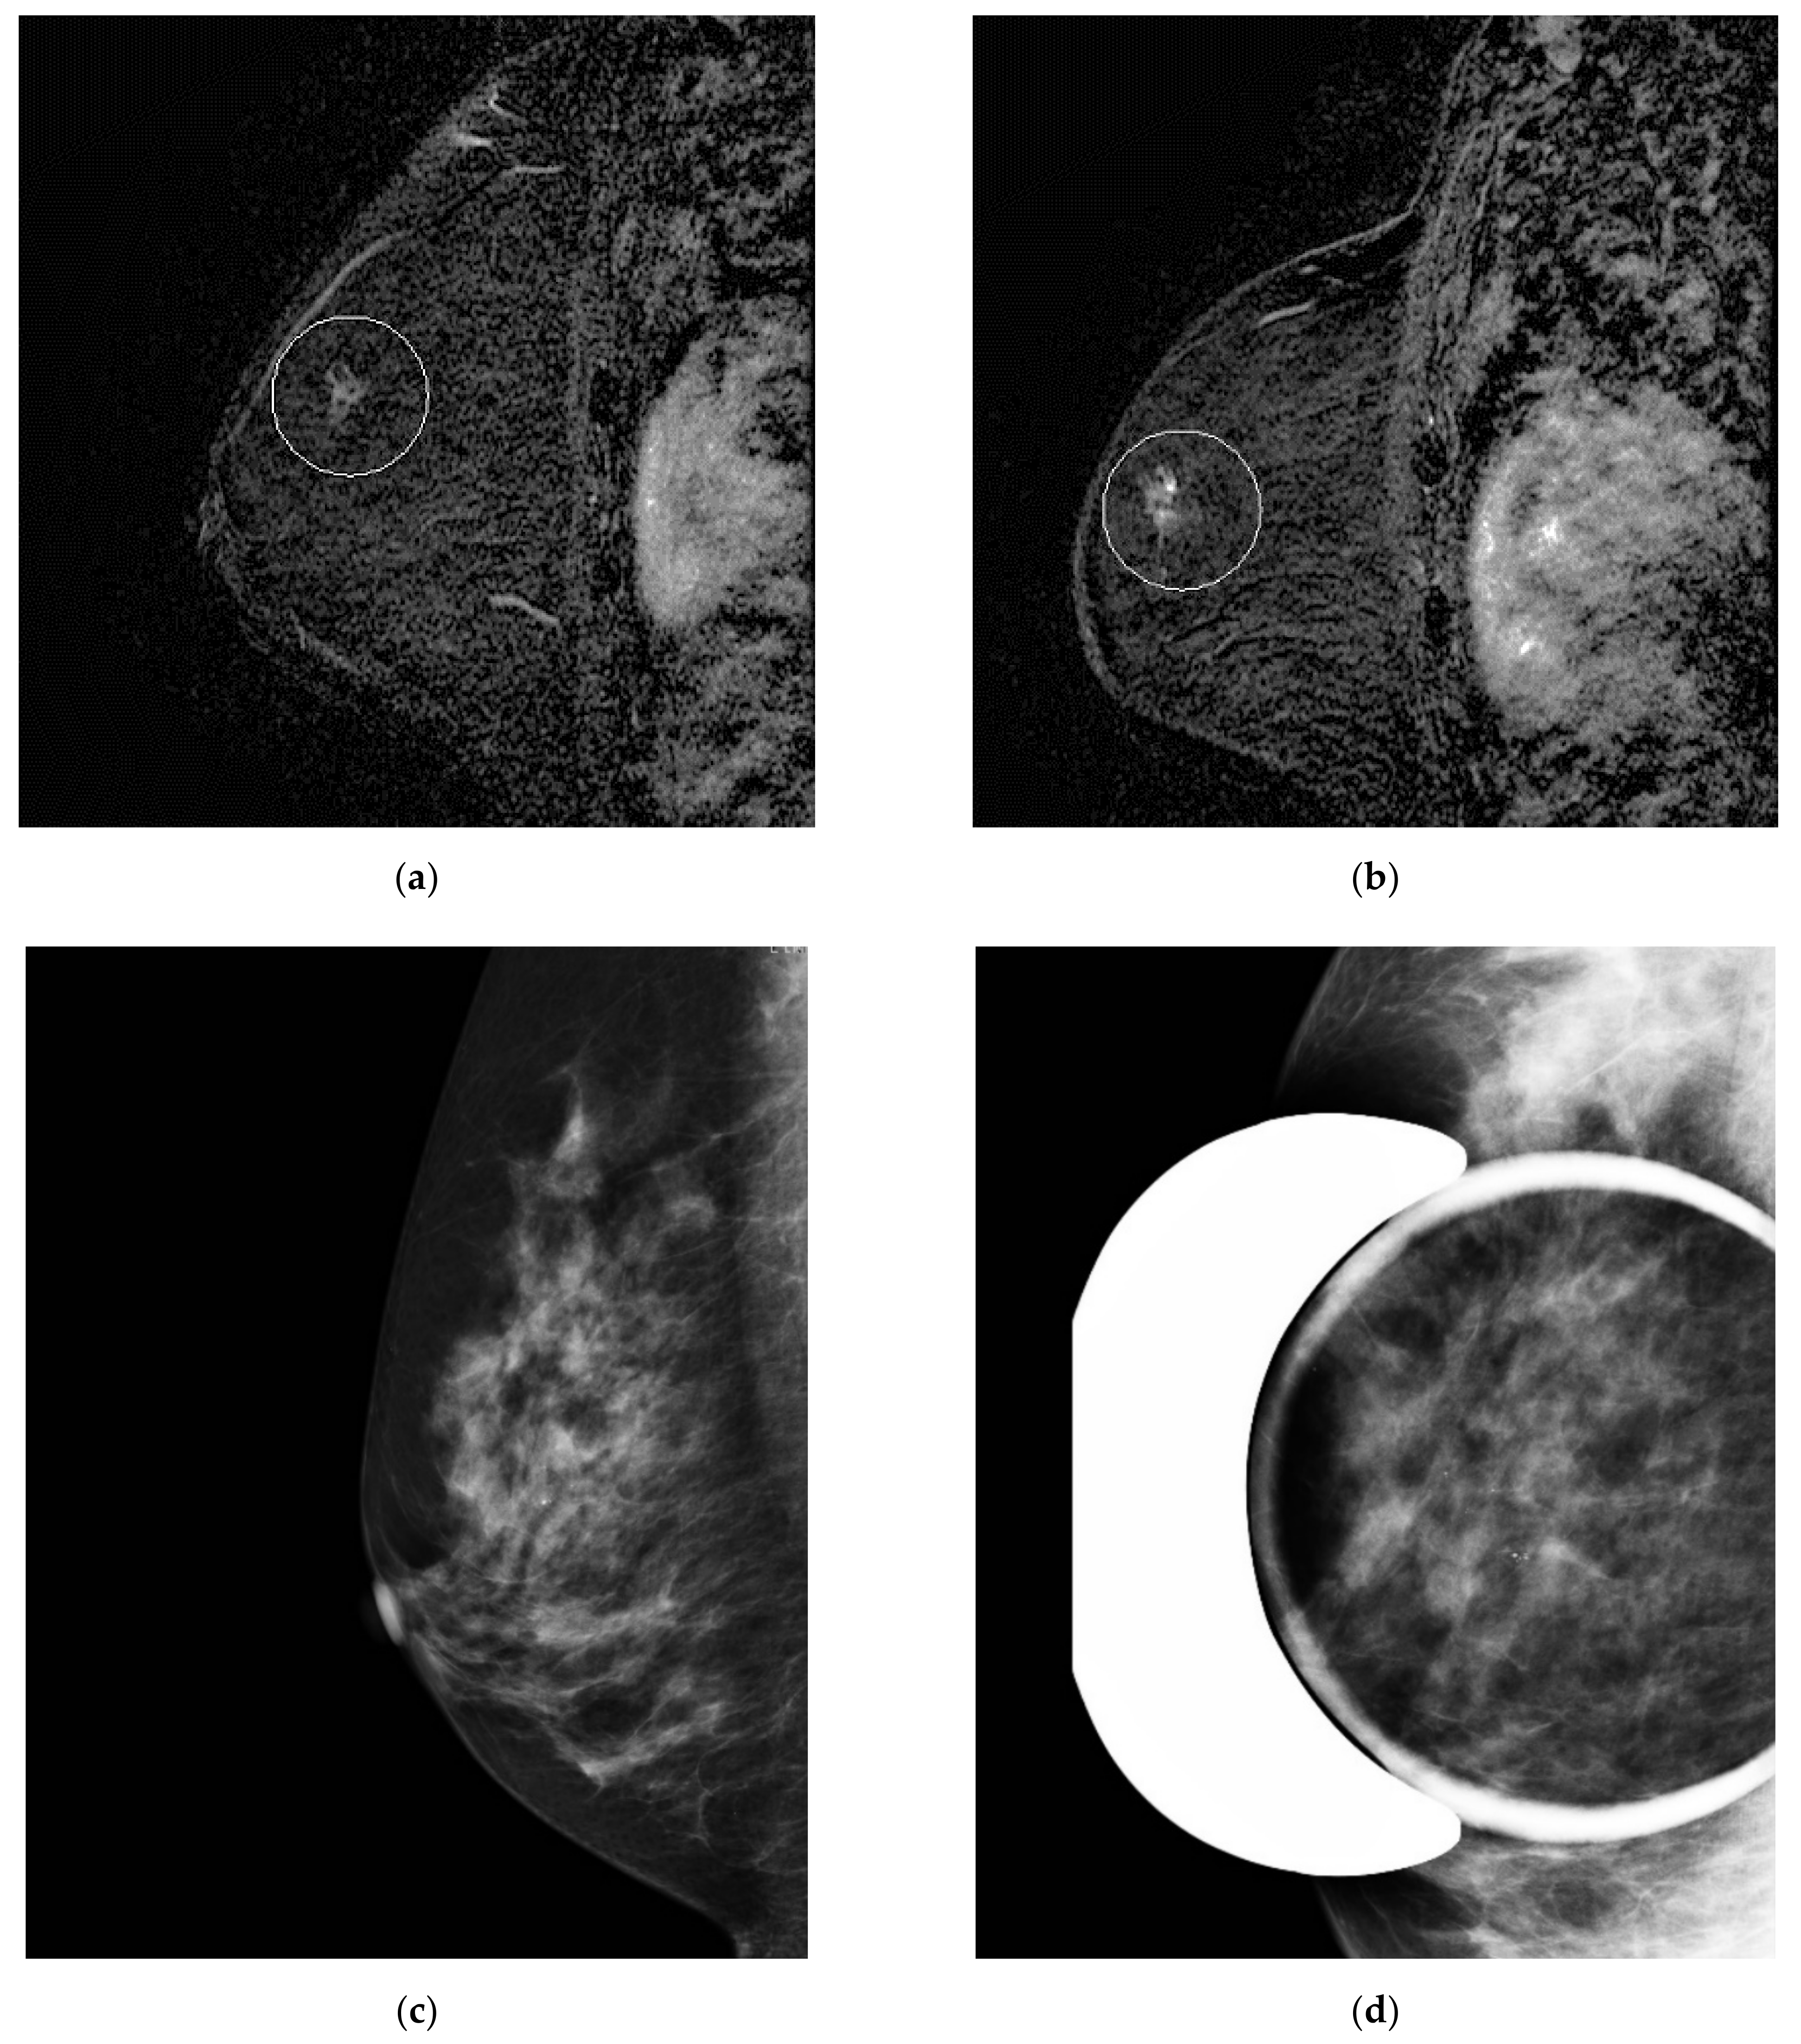

Figure 3.

Misinterpreted stable non-mass enhancement between (a) MR A and (b) MR B. Calcifications were visualized in the same location and increasing in number on (c) the concomitant mammogram and (d) magnification views.